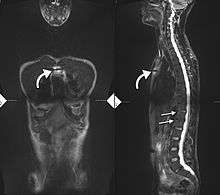

There is no direct test to diagnose AS. The Schober's test is a useful clinical measure of flexion of the lumbar spine performed during the physical examination.[11] Magnetic resonance imaging (MRI), and X-ray studies of the spine, which show characteristic spinal changes and inflammation of the sacroiliac joint, combined with a genetic marker blood test are the major diagnostic tools.

Radiographic features

- The earliest changes in the sacroiliac joints demonstrable by plain x–ray shows erosions and sclerosis.

- Progression of the erosions leads to pseudo-widening of the joint space and bony ankylosis.

- X-ray spine can reveal squaring of vertebrae with spine ossification with fibrous band run longitudinally called syndesmophyte while producing bamboo spine appearance.

- A drawback of X-ray diagnosis is the signs and symptoms of AS have usually been established as long as 8–10 years prior to X-ray-evident changes occurring on a plain film X-ray, which means a delay of as long as 10 years before adequate therapies can be introduced. Options for earlier diagnosis are tomography and MRI of the sacroiliac joints, but the reliability of these tests is still unclear.

T1-weighted MRI with fat suppression after administration of gadolinium contrast showing sacroiliitis in a patient with ankylosing spondylitis